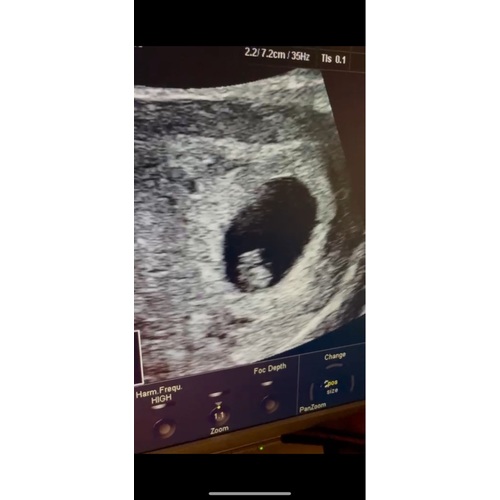

6w en 6d. Afgerond 7 weken haha, afgelopen dinsdag eerste echo gehad 😊